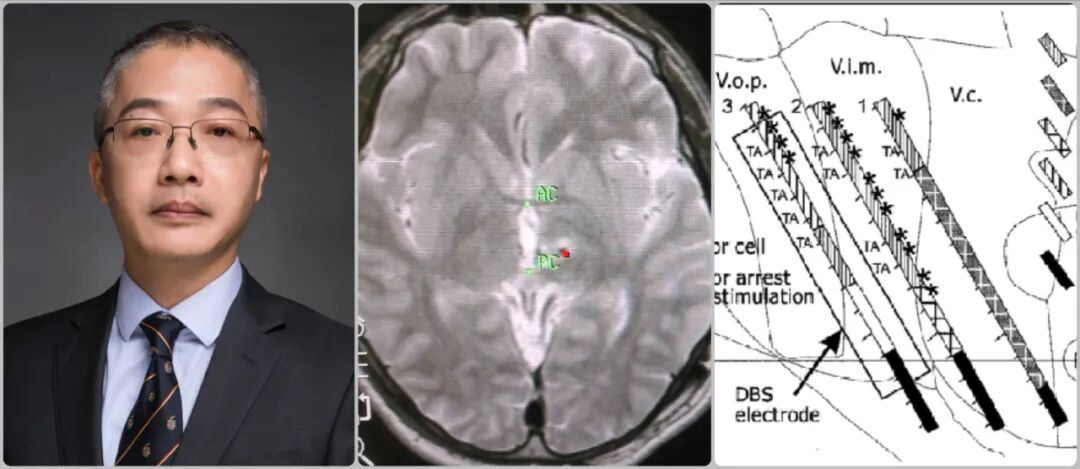

第633期-ROSA专栏|专访宣武医院吴浩:机器人辅助下置钉  神经纤维瘤脊柱侧弯从难治变可治